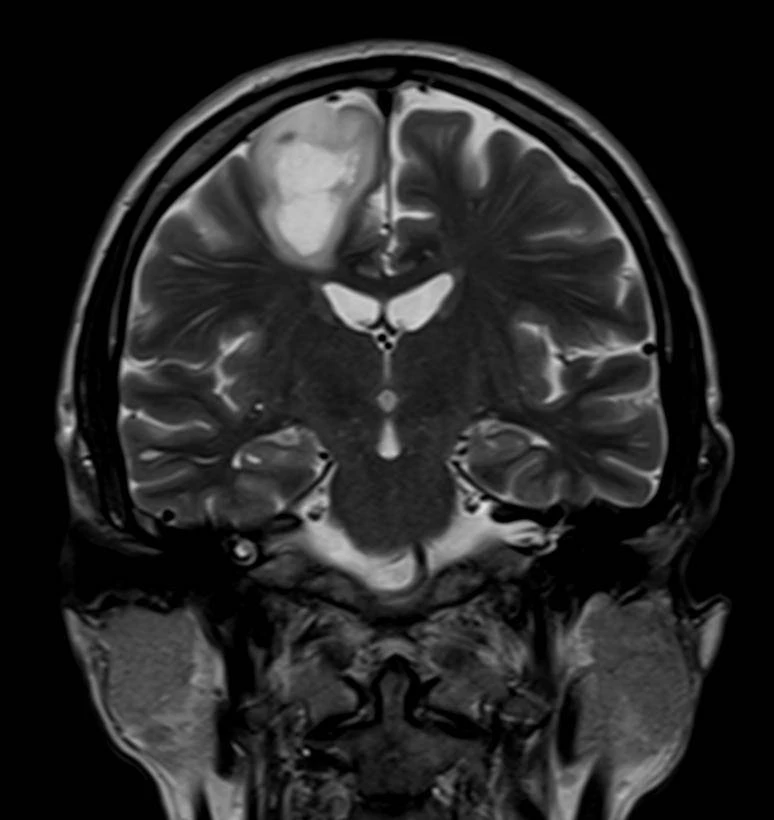

Семь менингиом и метастаз (рака молочной железы).

Четко видно, как по строению отличаются доброкачественные опухоли от злокачественных.

Первые яркие, четкие, шаровидные/полушаровидные, видно прикрепление широким основанием к костям, даже у самой мелкой.

А метастаз неровный, неяркий, нечеткий, неровный, из-за некроза, инвазии в мозг и перифокального отека.

Смотрим и запоминаем!